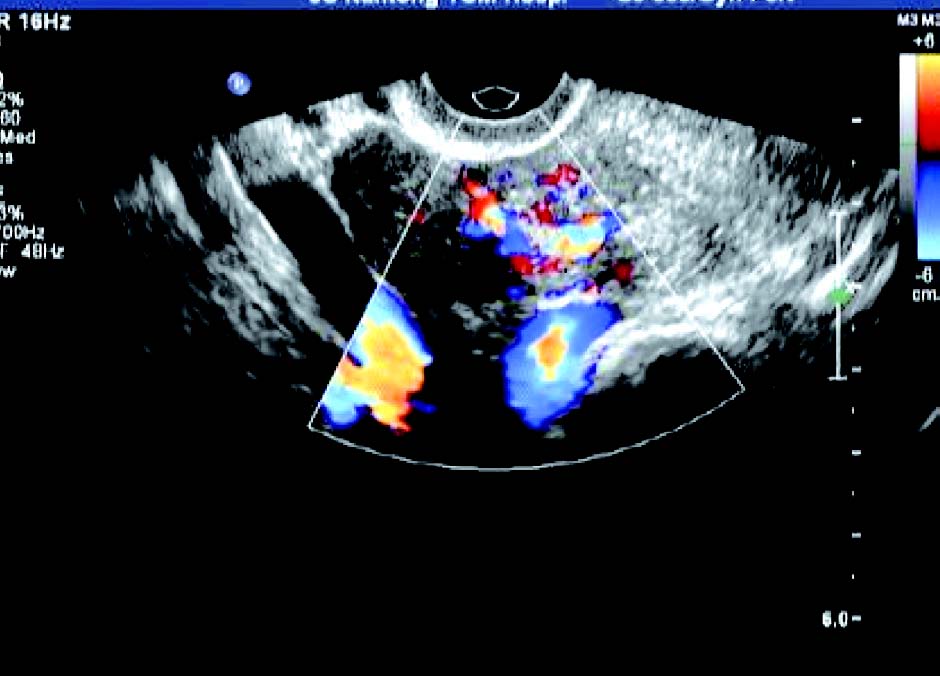

子宫增大,形态失常,浆膜向外呈圆形或半圆形突出,呈弱或中等回声,局部加压扫查,动态视察,瘤体与子宫无分离现象。CDFI 检测: 瘤周显现环状血流信号,并向瘤体延伸。浆膜下肌瘤突入子宫两侧阔韧带称为阔韧带肌瘤,常显示为子宫一侧实质性圆形肿物,体积较大,仅一蒂状与子宫相连,易变性;蒂部彩色血流信号来源于子宫,其彩色血流信号环绕瘤体。

2. 肌壁间肌瘤

多呈低回声,大小不一,包膜完整,瘤体与宫壁正常肌层间界限清晰,周围显示环状彩色血流信号。肌瘤较大时,可压迫和推挤宫腔,使宫腔内膜回声移位或变形。